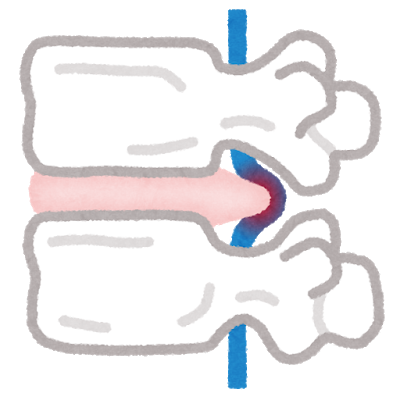

あぐらをかいて座る女性 写真素材フォトライブラリーは、日本のストックフォトサイトです。ロイヤリティーフリー画像を販売。動画素材はsサイズすべて無料。 s550円~ id: あぐらをかいて座る女性 はこちら縁側であぐらをかく和服姿の男性 の写真素材・イラスト素材|アマナイメージズ 縁側であぐらをかく和服姿の男性 の写真素材・イラスト素材。 アマナイメージズでは3000万点以上の高品質な写真素材・イラスト素材・動画素材が購入可能です。 ロイヤリティフリー作品だけでなくライツマネージド作品も豊富に取り揃えています。 椎間板ヘルニアが原因で、あぐらをかいて足がしびれる? あぐらの姿勢は通常、 椎間板ヘルニア の症状が楽になる姿勢なので可能性はとても低いと考えられます。ヘルニアで神経が圧迫されているためにしびれが出ているなら、日常生活のいろいろな場面でしびれや痛みを感じているは

あぐらをかくと足がしびれる 整体は御茶ノ水のカイロプラクティック 新御茶ノ水外来センターへ

あぐらをかくと足がしびれるのはがこれが原因 病気や対処法 あぐらをかけない人へ 気になる木を育てるブログ